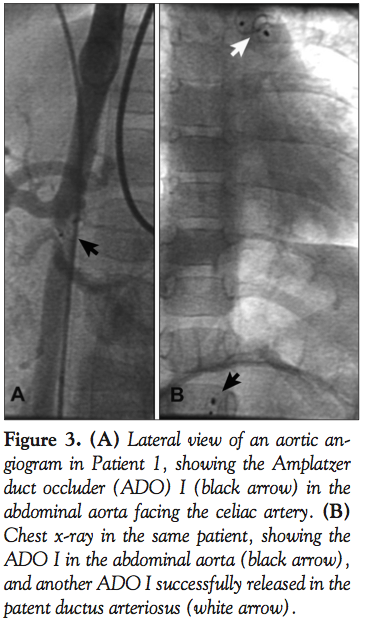

For the ADO I, immediate closure was achieved in 40% of the cases (30/74 patients), rising to 94.6% (70/74 patients) at 24 hours, and to 96% (71/74 patients) at 6 months. Thus, the ADO I failed to close the PDA in 3 patients. The first patient (Patient 1 in Table 2 and Figure 1) was a 3-year-old, 17 kg boy with a 4 mm type D PDA which was initially closed with an 8-6 ADO I. The Amplatzer asymptomatically migrated to the abdominal aorta before discharge from the hospital. The shunt seen on the follow-up serial echocardiograms was thought to

be a residual shunt, and the migration was diagnosed only 1 year later. We believe that this migration occurred on the second day, because the predischarge chest x-ray examined retrospectively 1 year later did not show the radio-opaque markers of the ADO in the usual position. The device was embedded asymptomatically in the abdominal aorta, facing the celiac artery (Figure 3A, black arrow). Attempts at its percutaneous removal 1 year later failed due to strong adhesions to the aortic wall; hence, it was left in place since it wasn’t obstructive. This failure was considered recovered, as the PDA was percutaneously closed using a 14-12 ADO I (Figure 3B); the device was oversized to achieve incomplete deployment of the aortic disc inside the PDA (Figure 4). The first ADO is still in the abdominal aorta with no gradient on the serial Doppler studies for 6 years now. The second patient (Patient 2 in Table 2 and Figure 1) was a 7-month-old who weighed 6.5 kg, with a 2.2-mm wide and 9-mm long type C PDA. When it was advanced and correctly positioned in the PDA, the 6-4 ADO I became severely kinked with a very narrow angle, and thus kept sliding backward and protruding into the pulmonary artery during every release attempt. The device wasn’t released, the procedure was abandoned, and the patient was referred for surgery 3 months later. This happened before the ADO II era. The third ADO I failure (Patient 3 in Table 2 and Figure 1) was a 6-month-old, 7 kg baby girl with a type B, 6.6 mm duct; the 10-8 ADO I totally obstructed the aortic flow and was retrieved before releasing. The patient was also referred for surgery.

Interestingly, all 3 recovered failures were attributed to migration of the device, and all 3 definite failures referred to surgery were due to the protrusion of the device, and obstruction of the aorta or pulmonary artery. Concerning migration, one may assume that if an ADO is completely deployed, secondary migration should be obviously due to the small size of the device relative to the diameter of the PDA; this assumption was confirmed in our series by the successful secondary occlusion of the ducts using larger devices in all 3 patients. The patient illustrating best the advantages of device oversizing was Patient 1. In this patient, the measured minimal diameter of the 20-mm long type D PDA was around 4 mm. An 8-6 ADO I was placed in the aortic restriction, which resulted in the migration of the device. This failure was recovered by modifying the deployment technique of the ADO I; the device was oversized on purpose (14-12 ADO I), to obtain an incomplete deployment of the aortic disc inside the duct. The excessive length of this PDA prevented protrusion of the device into the pulmonary artery after its release.3 This technique was successfully reiterated in other patients with type C ducts measuring more than 5 mm. However, care must be taken with device oversizing; generous oversizing may tear the duct wall. Oversizing needs also a small restriction area somewhere in the duct. In a 30 kg, 14-year-old patient with severe pulmonary hypertension and a short type A PDA, the ADO I was largely oversized, but normally deployed, so that the pulmonary narrowing transformed the pulmonary part of the device in a retention disc. This prevented aortic migration of the ADO that might have been facilitated by pulmonary hypertension. This technique is not applicable in small infants.